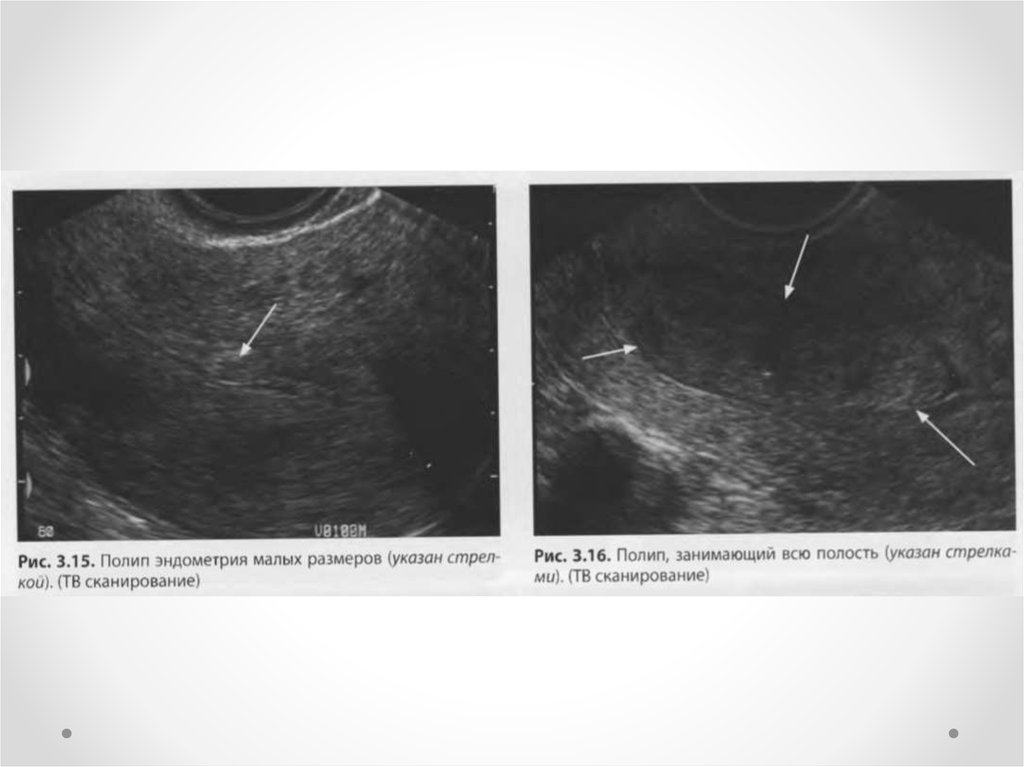

Медицинская диагностика: Гиперплазия эндометрия на УЗИ